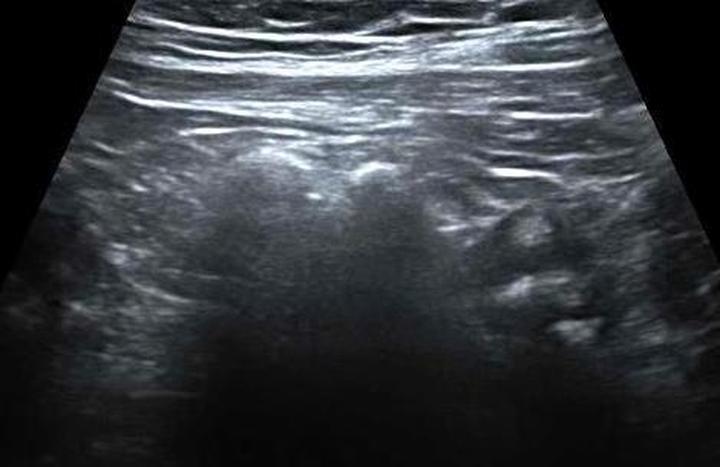

Ultrasonografia, znana w skrócie jako USG, stanowi jedno z badań, które od razu przychodzi na myśl, gdy rozważamy diagnostykę medyczną. Warto jednak zauważyć, że kiedy mówimy o wykrywaniu nowotworów, szczególnie raka jelita grubego, USG nie pokazuje pełni swoich możliwości. Ma swoje ograniczenia, zwłaszcza w przypadku małych zmian, a diagnostyka wczesnych stadiów nowotworów nie zagwarantuje najlepszych wyników. Możemy porównać USG do dobrego kucharza, który przyrządza znakomity obiad, ale zapomniał o soli – wszyscy odczuwają, że czegoś brakuje, ale nikt nie potrafi dokładnie zidentyfikować problemu.

W dodatku obrazowanie ultrasonograficzne charakteryzuje się szczególnymi cechami. Z łatwością wykrywa duże guzy, które mogłyby nawet zabierać głos w karaoke, natomiast rozpoznawanie subtelnych, małych zmian, które mogą w przyszłości przekształcić się w nowotwory, sprawia jej trudności. Dlatego poleganie wyłącznie na USG w kontekście wykrywania raka jelita grubego przypomina kupowanie losu na loterii – lepiej mieć różne metody w zasięgu ręki, aby zwiększyć swoje szanse na sukces. Warto więc rozważyć takie alternatywy, jak kolonoskopy, tomografy komputerowe czy rezonanse magnetyczne, które dostarczają znacznie więcej informacji niż wywiad w programie plotkarskim.

USG, czyli ultrasonografia, często zdobywa uznanie w gabinetach lekarskich, ponieważ to małe cudo technologii skanuje nasze wnętrzności za pomocą dźwięków. Kiedy jednak mowa o diagnozowaniu raka jelita grubego, nie można uznać tej metody za jedną z najskuteczniejszych! Wbrew powszechnym przekonaniom, USG nie potrafi precyzyjnie ukazać, co dzieje się z ściankami jelit. Niezbyt sprawiedliwe okazuje się także porównywanie go z kolonoskopią, która niczym detektyw bada wnętrze jelit w poszukiwaniu podejrzanych zmian. Jeśli obawiasz się drobnych „niedogodności” związanych z kolonoskopią, wówczas USG może być tymczasowym rozwiązaniem, ale niechętnym w walce z nowotworami.

Co więcej, warto podkreślić, że USG często serwuje zaskakujące wyniki, ponieważ skutecznie diagnozuje tylko spore guzy w zaawansowanym stadium. Można to porównać do sytuacji, w której dostrzegamy biegnącą grupę sportowców na boisku, zamiast zauważać małe, ale groźne zapowiedzi ich treningów. Dlatego w poszukiwaniach raka jelita grubego lepiej zaufać kolonoskopii, która z całą pewnością umożliwia usunięcie polipów oraz pobranie próbek do analizy. Bez wątpienia jest to znacznie bardziej interesujące niż obserwowanie wydarzeń za pomocą USG!